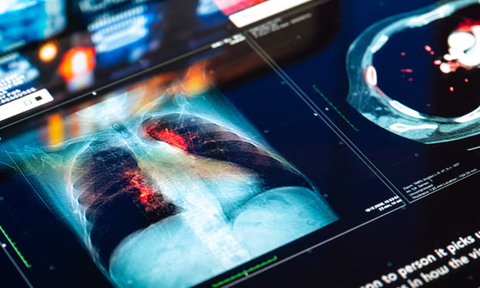

Γιατί όλο και περισσότερες νεαρές γυναίκες διαγιγνώσκονται με καρκίνο του στομάχου;

Η αύξηση στις νεότερες γυναίκες είναι ιδιαίτερα ανησυχητική επειδή η ασθένειά τους τείνει να είναι πιο λοιμώδης.

Πριν από μια δεκαετία σχεδόν, η Shria Kumar, γαστρεντερολόγος και ερευνήτρια στο Πανεπιστήμιο του Μαϊάμι, άρχισε να παρατηρεί κάτι ανησυχητικό. Μερικοί από τους ασθενείς της με καρκίνο του στομάχου ήταν πολύ νεότεροι απ’ ό,τι συνήθως και πολλοί από αυτούς ήταν γυναίκες. Είναι μια τάση που συνεχίζεται μέχρι σήμερα.

Οι επιστήμονες είναι ανήσυχοι προσπαθώντας να καταλάβουν γιατί συμβαίνει αυτό. Εξετάζοντας μητρώα ασθενών με καρκίνο σε πολλές πολιτείες στις ΗΠΑ, οι ερευνητές κατέληξαν στο συμπέρασμα ότι ο καρκίνος του στομάχου αυξάνεται με μεγαλύτερο ρυθμό στις νεότερες γυναίκες. Κατά τη διάρκεια σχεδόν δύο δεκαετιών, τα ποσοστά για τις γυναίκες κάτω των 55 ετών αυξήθηκαν κατά 3%, δηλαδή διπλάσιο από το αντίστοιχο για τους νεότερους άνδρες. Αυτό συμβαίνει καθώς μειώνονται παράλληλα, τα ποσοστά για τους ασθενείς με μεγαλύτερη ηλικία. Η αύξηση στις νεαρές γυναίκες συμβαίνει κυρίως σε μη Ισπανόφωνες λευκές, μια πληθυσμιακή ομάδα που παραδοσιακά εμφάνιζε λιγότερες πιθανότητες εμφάνισης της νόσου συγκριτικά με μαύρες γυναίκες, Ισπανόφωνες ή Ασιάτισσες.

Στις ΗΠΑ, οι άνδρες άνω των 55 εξακολουθούν να αποτελούν το μεγαλύτερο ποσοστό των ασθενών με καρκίνο του στομάχου, αλλά η αύξηση στις νεότερες γυναίκες είναι ιδιαίτερα ανησυχητική επειδή η ασθένειά τους τείνει να είναι πιο λοιμώδης.

«Αυτοί οι όγκοι είναι πιο προχωρημένοι στη διάγνωση και είναι πιο επιθετικοί», γεγονός που οδηγεί σε χειρότερες προγνώσεις, είπε η Kumar.

Το συνολικό ποσοστό πενταετούς επιβίωσης για τον καρκίνο του στομάχου στις ΗΠΑ είναι 36%. Ο αριθμός αυτός μειώνεται τα τελευταία χρόνια, ειδικά στους Ασιάτες και τους Μαύρους Αμερικανούς. Αλλά για τα άτομα που διαγνώστηκαν μετά την εξάπλωση του καρκίνου – ένα πιθανό σενάριο για τα νεότερα άτομα με πιο επιθετικούς όγκους- το ποσοστό επιβίωσης είναι μόλις 6,6%.